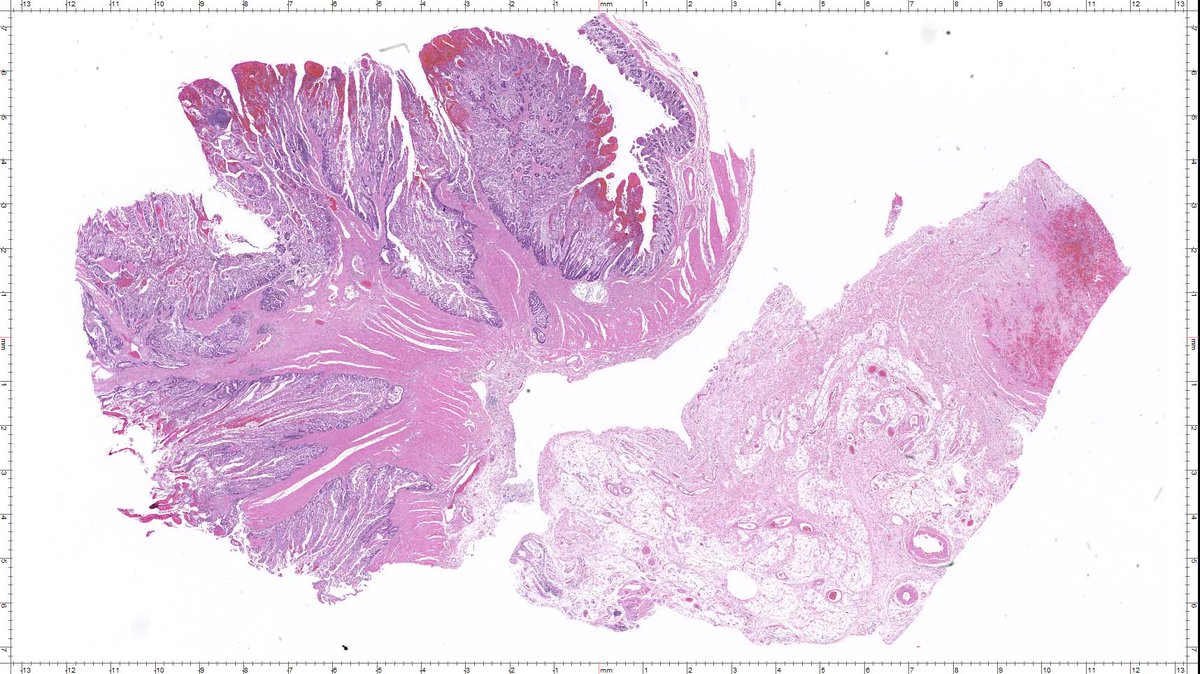

Here's an invasive tumor of the colon that I found this morning! This case is older than the majority of you - by a couple of decades! this one is special!! #GIpath